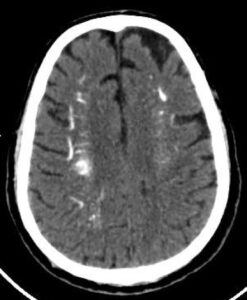

CASE 6- FAHR’S DISEASE

Near symmetric patchy calcifications are seen in bilateral cerebral and cerebellar hemispheres including:

- Bilateral basal ganglia

- Thalami

- Dentate nuclei

- Bilateral corona radiata.